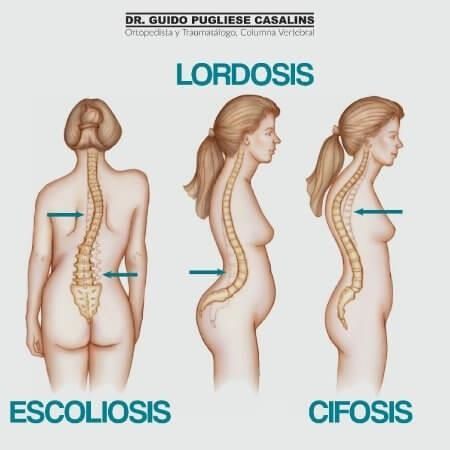

Ortopedista y traumatólogoOrtopedista de columna vertebralEscoliosis

Las especialidades de Dr. Guido Pugliese Casalins son: Ortopedista y traumatólogo, Ortopedista de columna vertebral, Escoliosis.